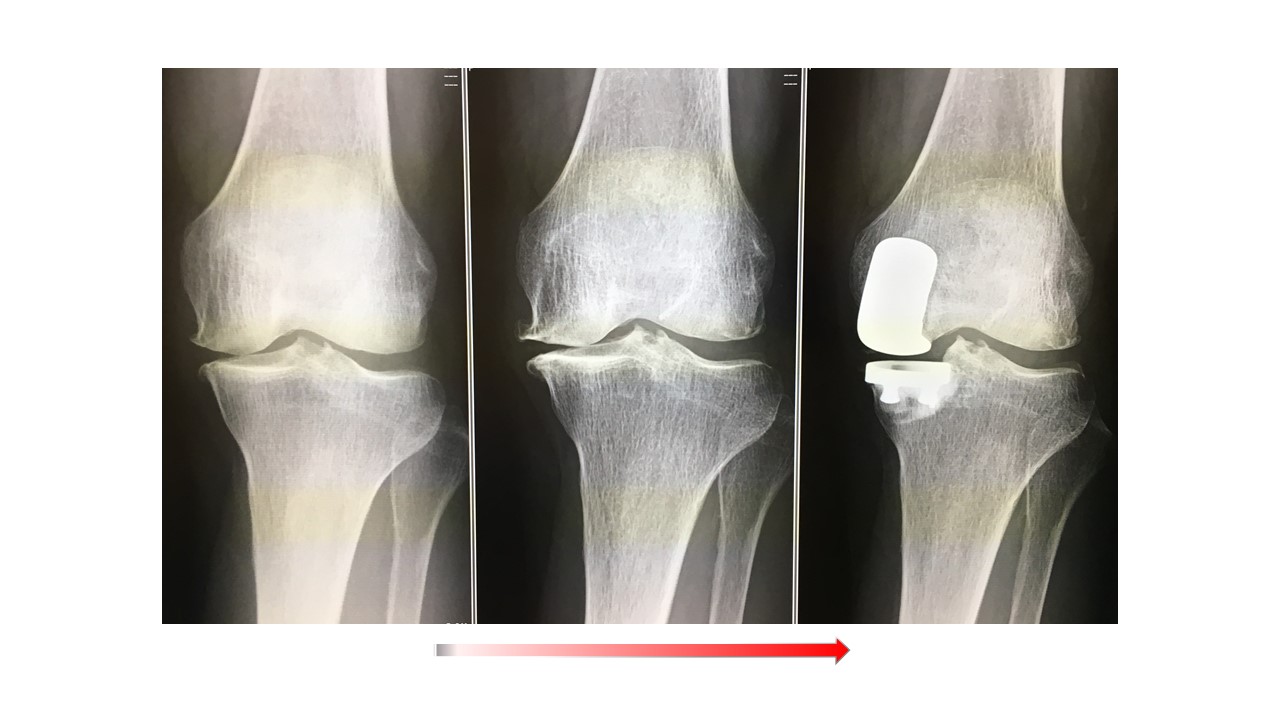

人工膝関節全置換術(単顆置換術)

人工膝関節全置換術(Total knee arthroplasty、TKA)ではナビゲーションシステムを使用して手術を行っています。より良い術後の満足度を得るため、生理的な膝のバランス、アライメントなどを考慮に入れた上で、術中の膝の状態をみながら、最適なインプラントの設置位置を決めて手術を行っています。そのため以前に比べてより使い易く違和感の少ない人工膝の再現が可能になっています。これらの術前検査として、立位での下肢全長のレントゲン検査やMRI検査、骨密度検査等も行いながら、最適なインプラントの選択を行います。さらに長期的には良好な骨の状態を保つことが重要ですので、術後も骨粗鬆症薬等につき外来でフォローアップ致します。紹介受診の場合はかかりつけのクリニックで骨粗鬆症薬の投薬を継続頂いてます。